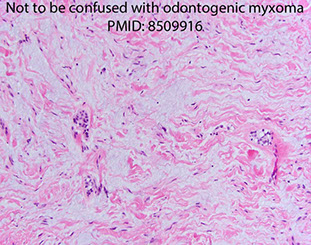

Subacute necrotizing sialadenitis of the left palate c focal acinar necrosis (stars)

Subacute necrotizing sialadentiis